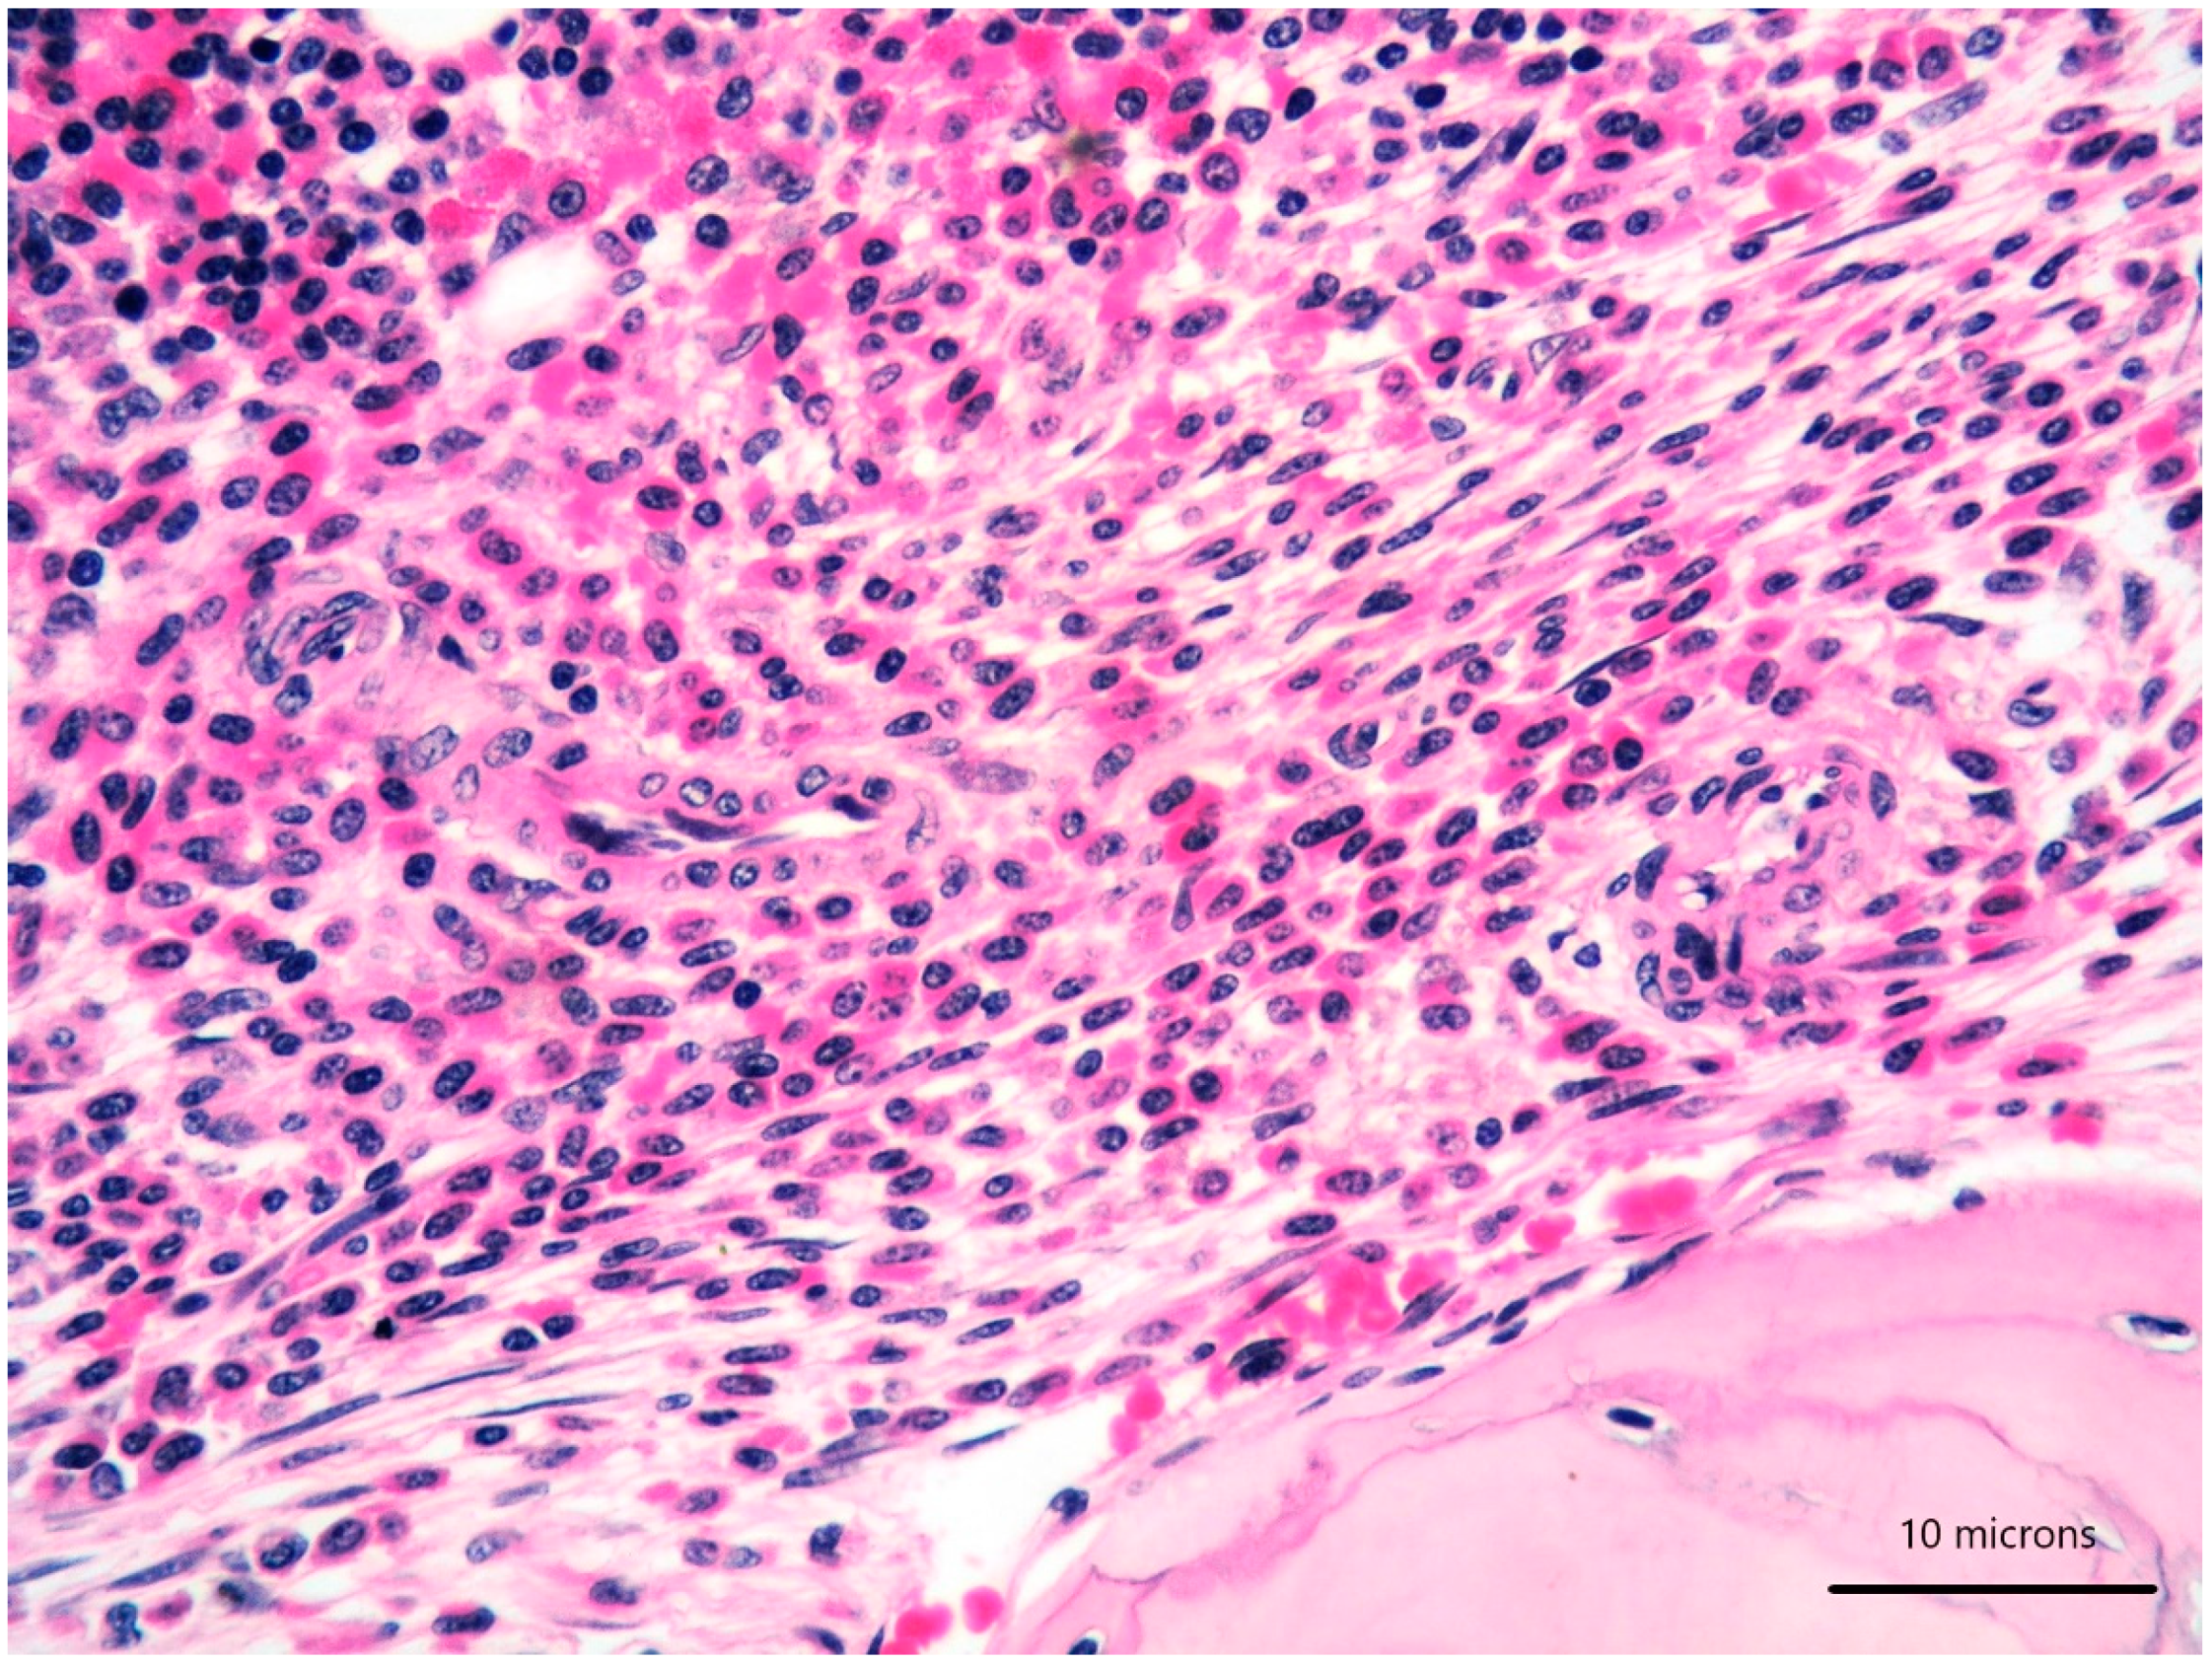

A 79-year-old woman was referred for a long history of peripheral eosinophilia. She underwent right hemicolectomy for colonic polyposis a few years before. Laboratory tests disclosed mild macrocitic anaemia (Hb 10.4 g/dL, MCV 93%) and eosinophilia (leukocytes 3360/mmc, eosinophils 30%). β2 microglobulin (3256 ng/dL; reference range 1010–1730) and serum tryptase (138 ng/L; reference range 0–11.4) were elevated. Serum immunofixation revealed IgA/kappa monoclonal protein (21 g/L). Bence-Jones protein was positive. Bone marrow (BM) biopsy revealed two neoplastic components. Low- and high-power views of haematoxylin and eosin sections showed cohesive paratrabecular aggregates of bland-looking, spindle-shaped cells (

Figure 1;

Figure 2 lower part) positive for CD117 (

Figure 3), tryptase and CD25 representing 20% of marrow cellularity. Aggregates of mature plasma cells (

Figure 1;

Figure 2 upper part) positive for CD138 (

Figure 4), MUM1/IRF4 and kappa light chain occupied 40% of the remaining bone marrow. Bone marrow aspirate confirmed the presence of the two neoplastic components (

Figure 5). KITD816V mutation was detected by DHPLC and confirmed by Sanger sequencing; TET2 mutation was identified using DNA sequence analysis on marrow aspirate. Monoallelic deletion of TP53/17p13 and trisomy of ATM/11q23 was detected by FISH analysis on BM enriched with plasma cells using CD138+ magnetic Micro-Beads, respectively, in 39% and 94% of nuclei. RUNX1, ASXL1, SRSF2 and U2AF1 were unmutated. Osteoporosis was identified by full skeletal X-rays and MRI. The case was referred to as SM with concomitant smoldering MM.

The diagnosis of SM was proposed owing to the fulfilment of the major diagnostic criteria (multifocal, dense, compact aggregates in bone marrow and/or extra-cutaneous organs) and three of the minor criteria (KIT D816V mutation, CD25 expression, serum tryptase level exceeding 20 ng/mL) combined with the presence of a C finding (organ involvement with loss of function: intestinal mastocytosis with clinical malabsorption identified in the previous colectomy specimen) [

1]. Due to the bone marrow findings, along with the absence of myeloma-defining events (frank anaemia, hypercalcemia, lytic bone lesions, renal insufficiency secondary to myeloma, recurrent bacterial infections, blood hyperviscosity, paraneoplastic neuropathy, signs of associated amyloidosis, spinal osseous lesions at MRI), our patient fitted into the diagnosis of smoldering MM.